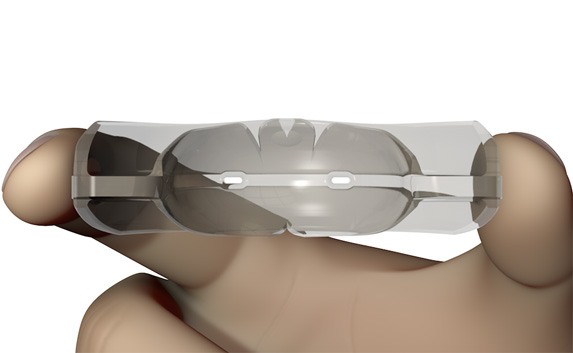

The TMJ Appliance®, which does not require any special fitting, is designed to act as an initial diagnostic and treatment tool for TMJ disorder. It works by decompressing the temporomandibular joint (TMJ), helps to correct mouth breathing and tongue posture habits, as well as limits bruxing. The TMJ Appliance® achieves TMJ disorder symptom relief immediately by alleviating pressure on the TMJ and relaxes the muscles around the jaw and neck.